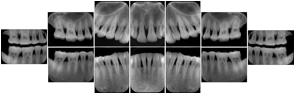

OO.1.3 Cardiology

Cardiac stress testing acquires images in at least two patient states, rest and stress, and typically with several different views of the heart to highlight function of different cardiac anatomic regions. Image review typically involves simultaneous display of the same anatomy at two patient states, or multiple anatomic views at one patient state, or even simultaneous display of multiple anatomic views at multiple states. This applies to all cardiac imaging modalities, including ultrasound, nuclear, and MR. The American College of Cardiology and American Society of Nuclear Medicine have adopted standard display layouts for nuclear cardiology rest-stress studies.

Stress Echocardiography Structured Display

Figure OO-5. Stress Echocardiography Structured Display

Stress-Rest Nuclear Cardiography Structured Display

Figure OO-6. Stress-Rest Nuclear Cardiography Structured Display